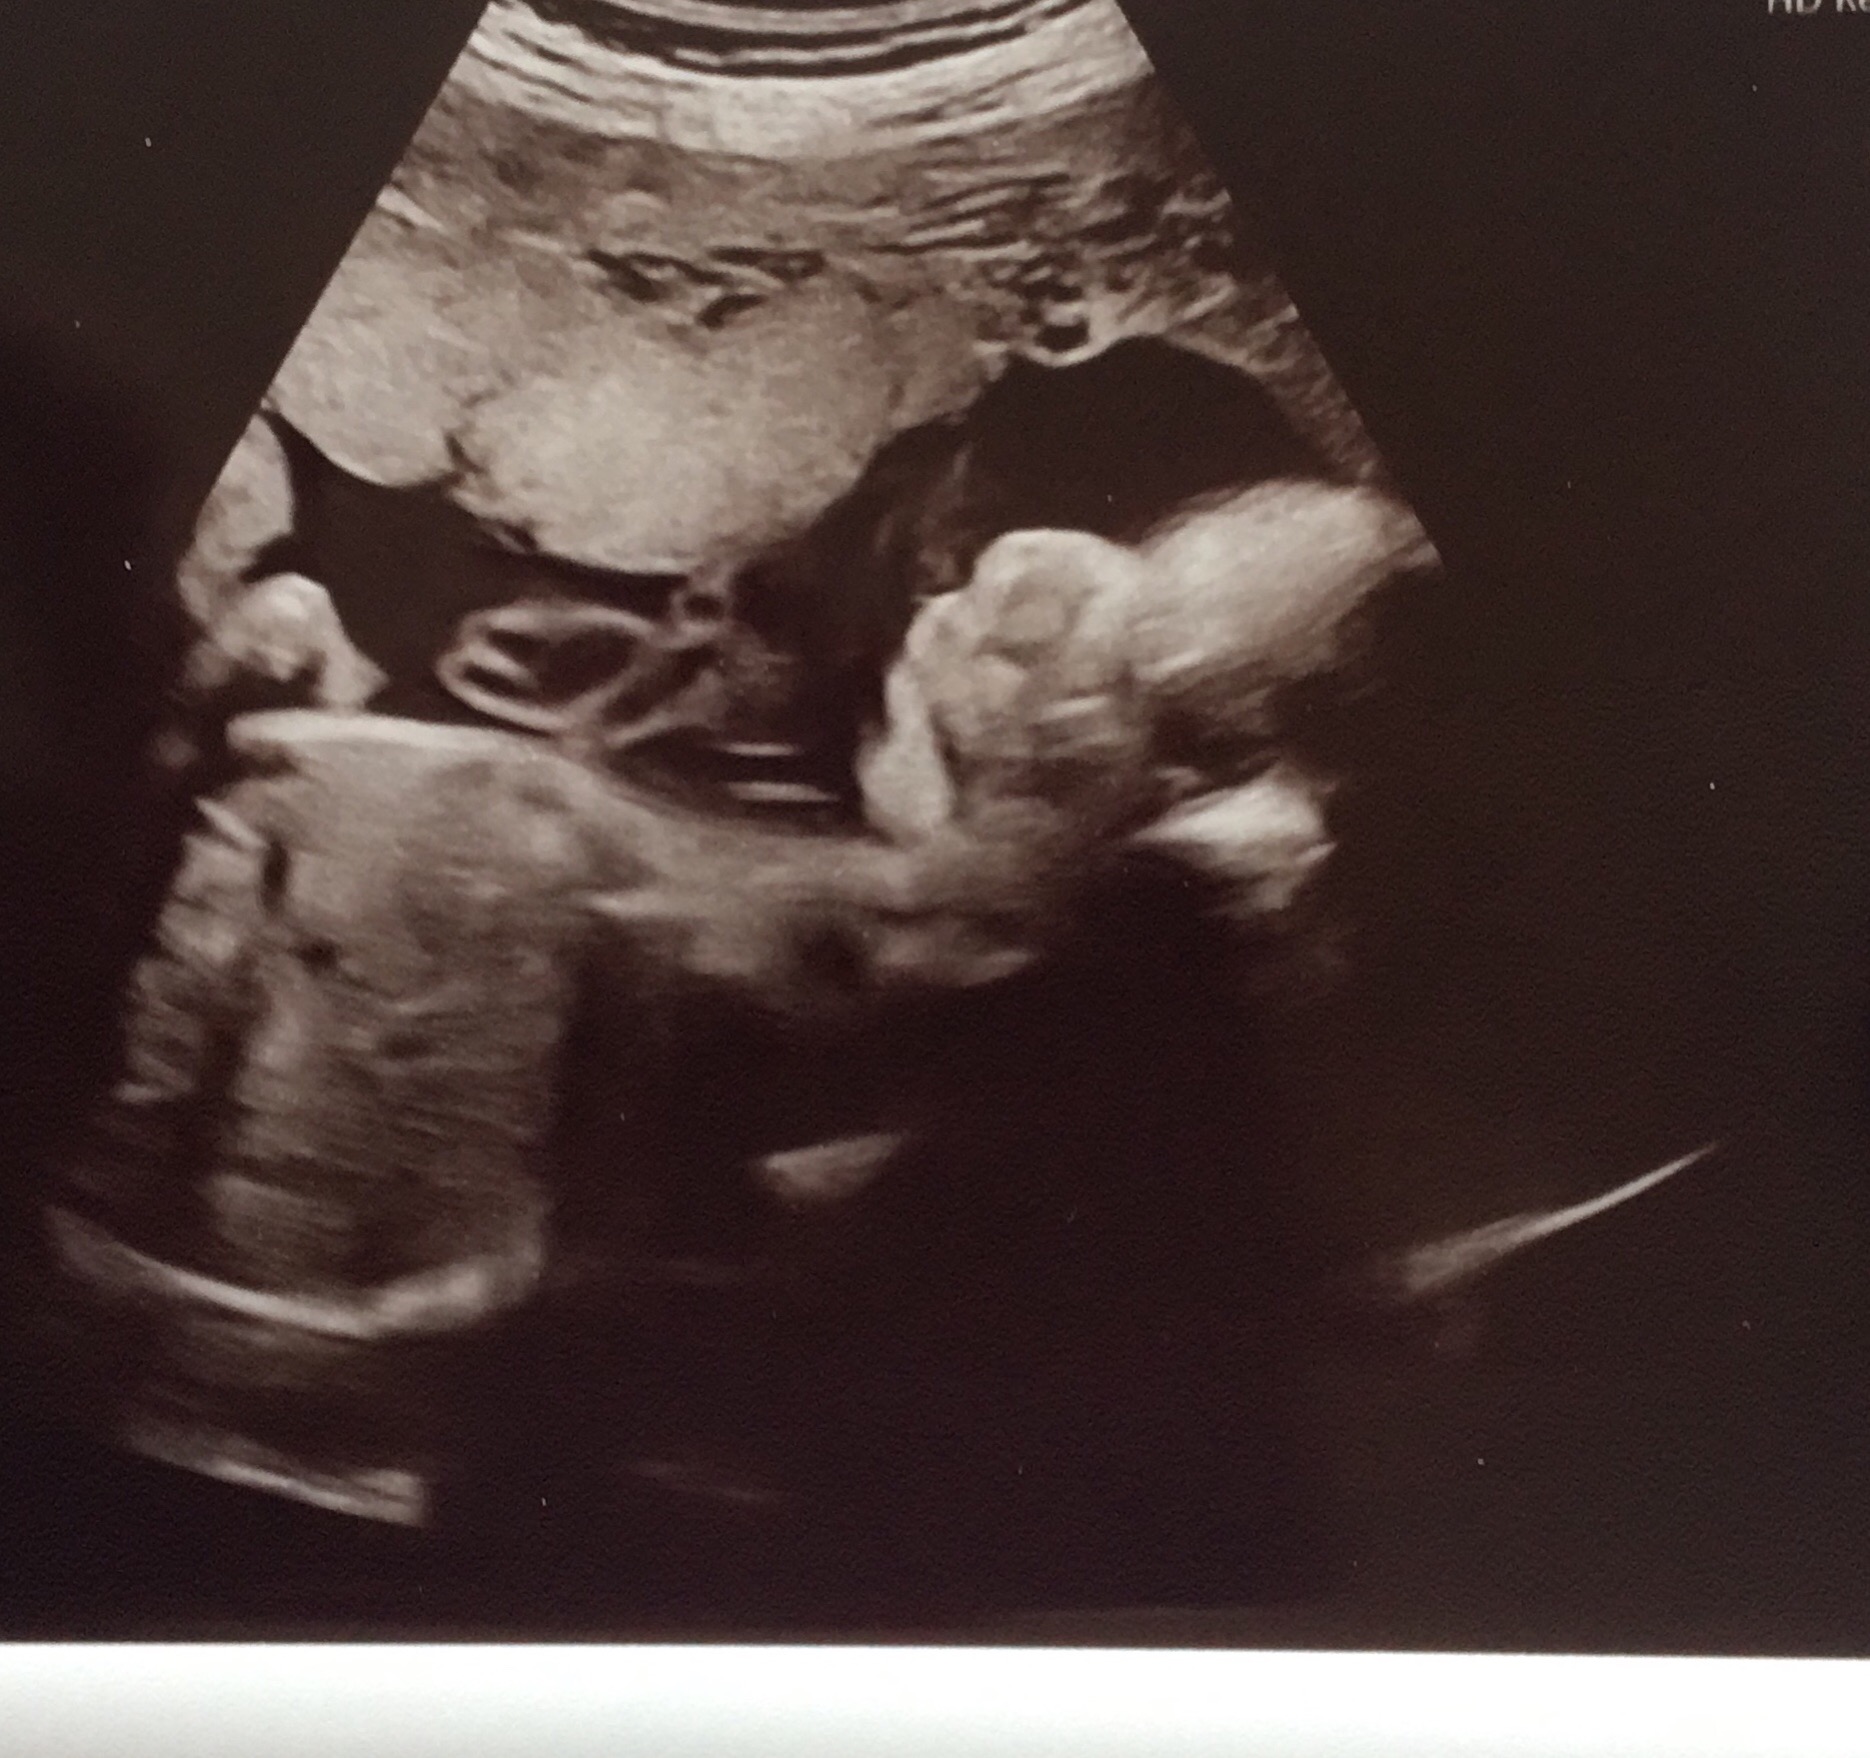

Had my 28 week ultrasound Baby was quite uncooperative and we couldnt get a good image of his face We got two, and can make out his chin and lips a bit, but his nose looks very skeletonish, almost like there is a big bump at the top (like a little hump!) The tech said she couldnt get a good nose shot, and it is quite blurred in the pic.

I had a 32 week ultrasound today my babies profile looked as though it had a gigantic pinnochio noseit kinda freaked me and my boyfriend out!.

Siehe Bild Ultraschall Grosse Nase Schwangerschaft Ssw

Ultraschall Vom Baby Hasslich Liliput Lounge